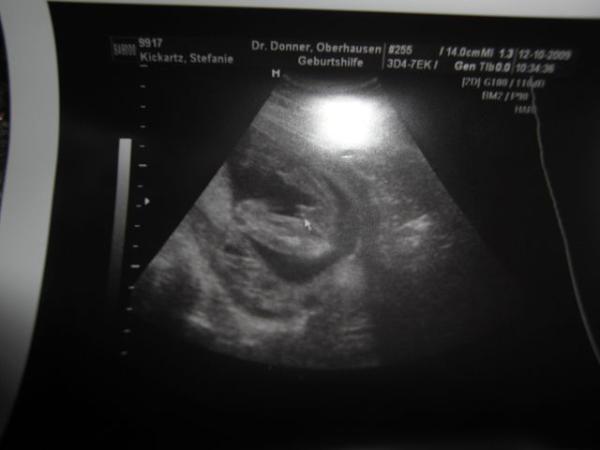

So ihr lieben da bin ich wieder Also erstmal es ist alles in ordnung,Blutdruck 120/80, hab 1kg zugenommen,Eisenwert ist super 14,6. Dann hatte ich ja das 2te Screening folgende Werte hat mein Bauchzwerg da BPD = 4,8 FOD/KU = 5,7 ATD = 4,3 FL =3,0 Und ein Outing gab es auch es wird ein Babyboy Beweissfoto hängt mit an. Wir freuen uns tierisch nach unserer Tochter nun einen Sohn zu bekommen. Nächste VU ist am 9.11.2009 Und ich habe schon einen Termin für den 3D/4D Ultraschall der ist am 10.12.2009. lg Steffi mit Babyboy inside

Bild zu VU Bericht+Outing :-) - Forum für März - Mamis